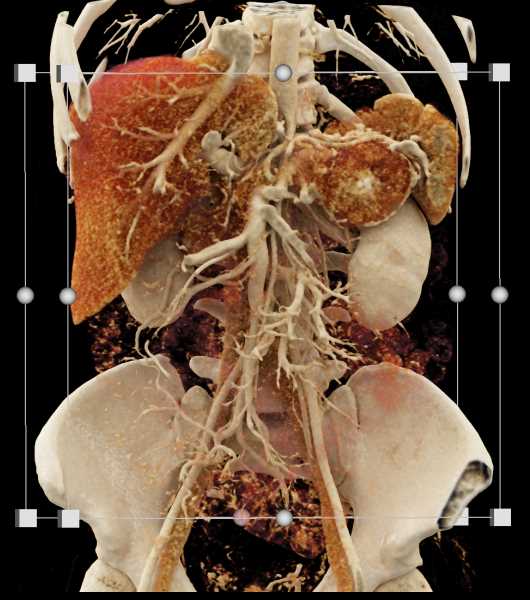

Neuroendocrine Tumor Pancreas